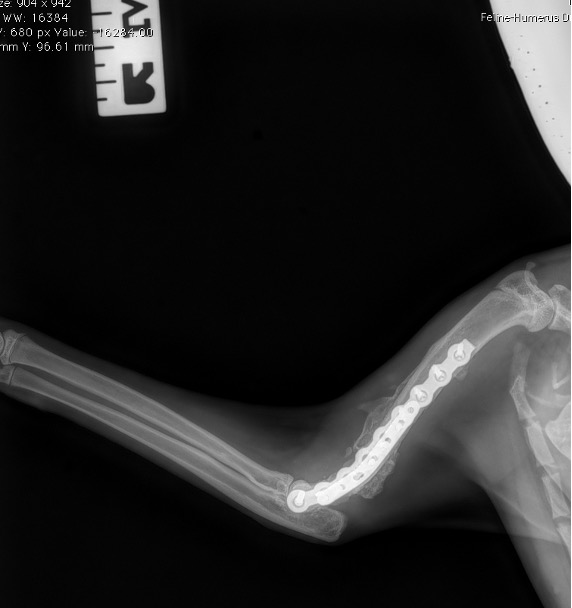

L’avènement récent des plaques anatomiques constitue une nouvelle option dans le traitement de ces fractures : dans l’exemple 3 (chat Ragdoll), une plaque anatomique médiale de 2 mm acceptant des vis de 1,6 et 2 mm a été utilisée seule avec succès.

Exemple 3 :

Figure 10 : Opération

Figure 11 : Post-Op Immédiat